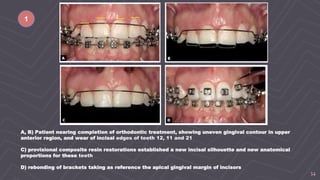

A, B) Patient nearing completion of orthodontic treatment, showing uneven gingival contour in upper

anterior region, and wear of incisal edges of teeth 12, 11 and 21

C) provisional composite resin restorations established a new incisal silhouette and new anatomical

proportions for these teeth

D) rebonding of brackets taking as reference the apical gingival margin of incisors